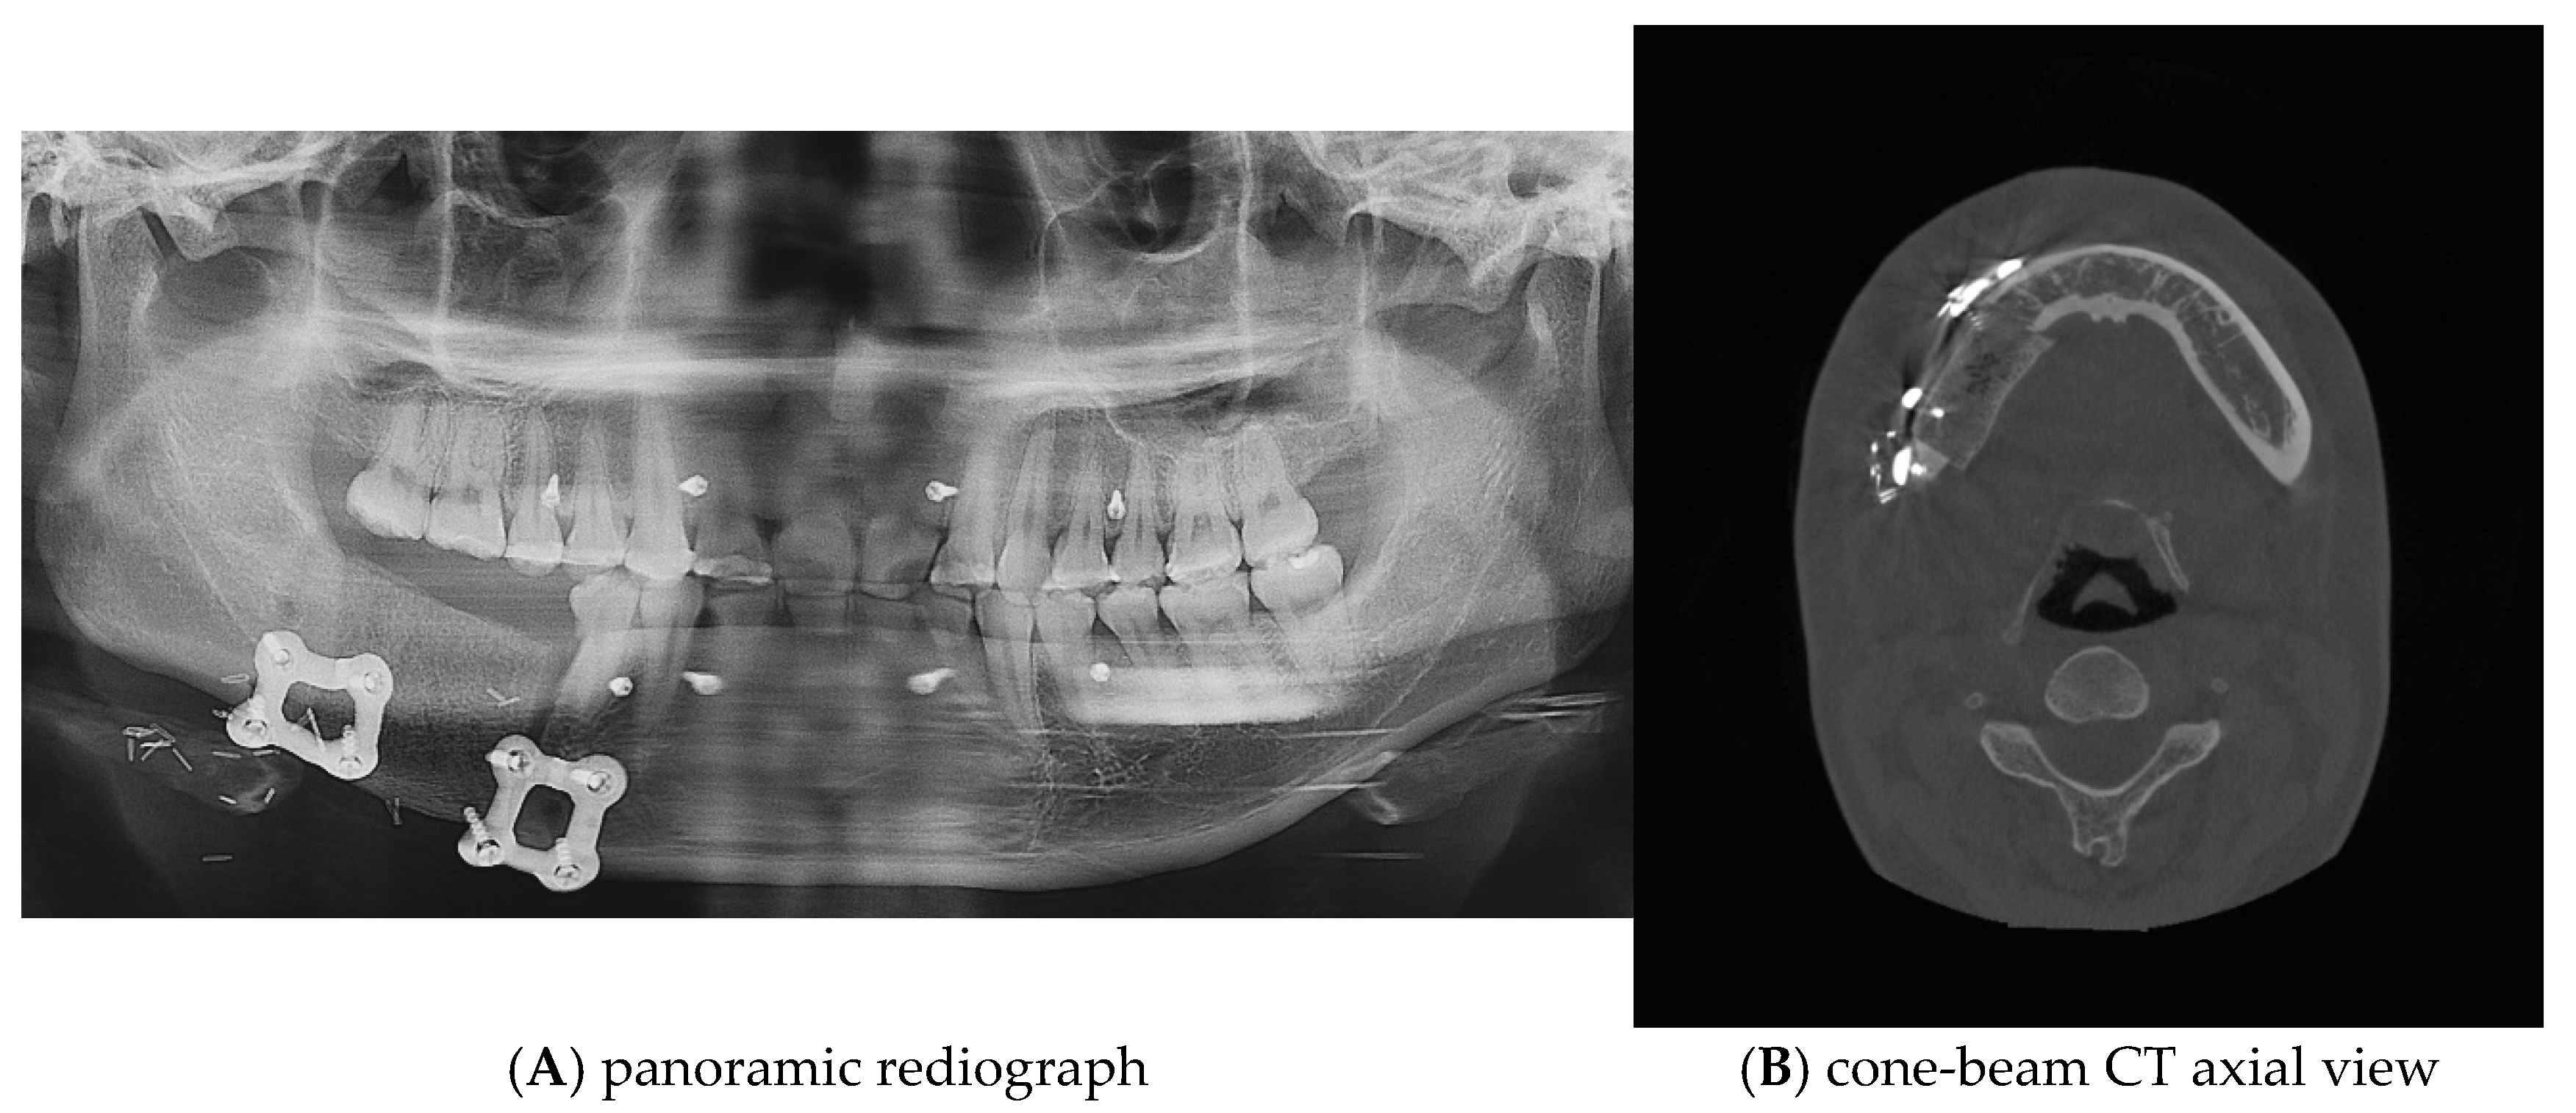

A 25-year-old female was referred to the Department of Oral and Maxillofacial Surgery from a local dental clinic with a primary concern of an intraosseous lesion located below the root apex of the right mandibular first molar. The patient did not report any clinical symptoms. Panorama revealed a multilocular radiolucent lesion with relatively well-defined borders and sclerotic margins in the region of the right mandibular molar. In addition, root resorption was observed in the right mandibular second premolar and first molar (Figure 1). Cone-beam computed tomography (CBCT) revealed thinning of the lingual cortical bone in the areas surrounding the right mandibular second premolar and first molar, as well as inferior displacement of the right mandibular canal (Figure 2). Both the right mandibular second premolar and first molar exhibited slight mobility and percussion sensitivity, while electric pulp testing was positive. Incisional biopsy was the ameloblastoma. To treat the lesion and minimize the risk of recurrence, resection and reconstruction were planned, and virtual surgical planning was performed in collaboration with the SEEANN solution (SEEANN solution, Seoul, Korea). To ensure accurate translation of the VSP to the actual surgery, template models were fabricated for preoperative simulation and intraoperative reference, and surgical guides were designed with multiple registration points for optimal positioning verification during the procedure.

Figure 1.

A multilocular radiolucent lesion with relatively well-defined borders and sclerotic margins in the right mandibular molar region, along with root resorption of the right mandibular second premolar and first molar (red arrow).

Figure 2.

Cone-beam computed tomography (CBCT) imaging revealed thinning of the lingual cortical bone in the region of the right mandibular second premolar and first molar, as well as inferior displacement of the right mandibular canal.